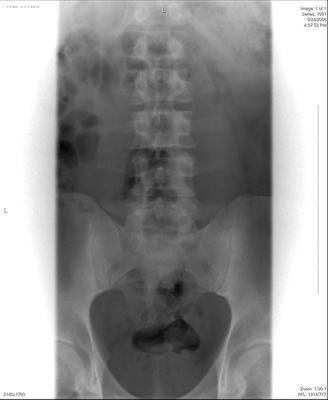

I'm 35 years old, male. Right hip pain, started as low back pain. Herniated disc L5S1, treated with ESI injections. Still have hip pain. Hurts when I flex my leg, SLR pain at about 45 degrees. My MRI and Xray are only of lumbar spine, however, do you see any abnormality of any bony or soft tissue of hip on these images? I understand it could be sciatica, which was the easiest thing they could come up with.

Two of the scan views are poor and I'm unable to determine what level; there's a suggestion of the fat squeezed out of the IVF on the right, but I wouldn't much store from that.

From what's visible of the hips they appear normal to me.

Please answer my questions fully. There were no hip x-rays attached, so I can't comment.